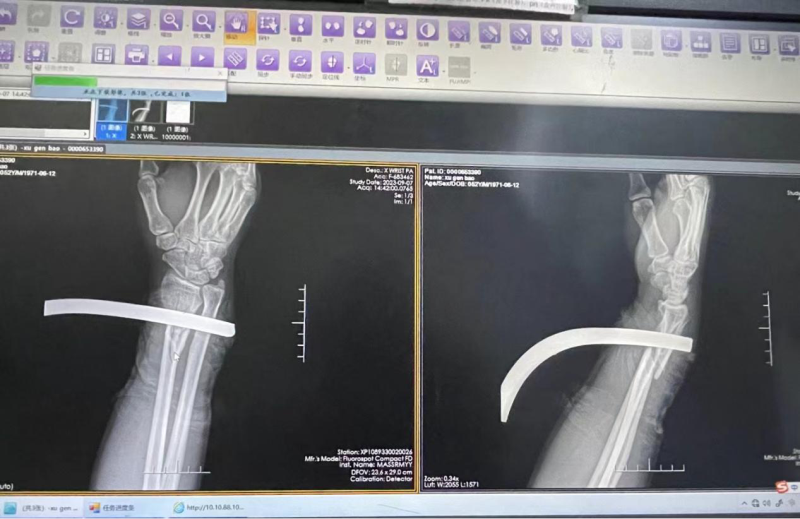

9月7日下午,隨著120的警報聲呼嘯而至,市人民醫(yī)院急診科接診一位中年男性患者。患者來時大汗淋漓,右腕可見鋼筋穿入,分診護士見狀立即通知急診骨科,并匯報科主任,同時迅速安排患者至搶救室監(jiān)測生命體征。骨科醫(yī)生到場會診后表示要先鋸斷鋼筋再行急診手術(shù),見患者表情痛苦不堪,急診科醫(yī)護不斷安慰患者,告知其不要緊張,患肢保持制動狀態(tài)。

十多分鐘后,消防隊攜帶大功率切割設(shè)備趕至搶救室,急診外科醫(yī)生和骨科醫(yī)生一起定位,隨著機器馬達的轟鳴聲,長達幾十公分的鋼筋應(yīng)聲而斷,在場所有醫(yī)護人員頓時松了口氣。隨后搶救團隊按照急診流程,一邊為患者采集全套血標(biāo)本,一邊聯(lián)系手術(shù)室、麻醉科,安排住院和急診手術(shù),僅半小時即將患者送往手術(shù)室進行手術(shù)治療。目前患者術(shù)后患肢功能恢復(fù)良好,已出院。